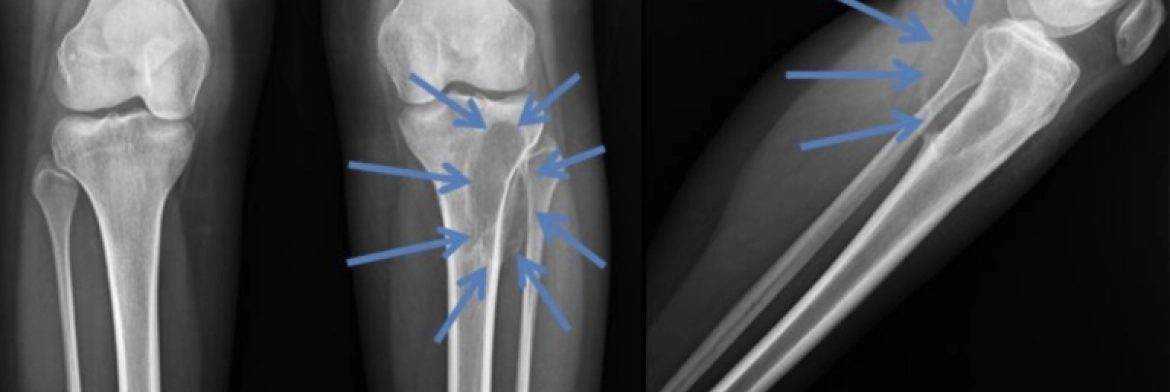

Resimde, tibia proksimalindeki bir Anevrizmal Kemik Kistinin sınırları direkt grafide mavi oklarla gösteriliyor.

Direkt Grafi

Ø Coğrafik ve ekzentrik yerleşimli radyolusen görünümdedirler.

Ø Çevreleyen kortekste yenikliğe ve genişlemeye sebep olabilir.

Ø En sık metafizde görülür.

Ø Çevrede benign karakterde bir periosteal reaksiyon görülebilir.

Ø Çevredeki kemik sklerotik görünümdedir.